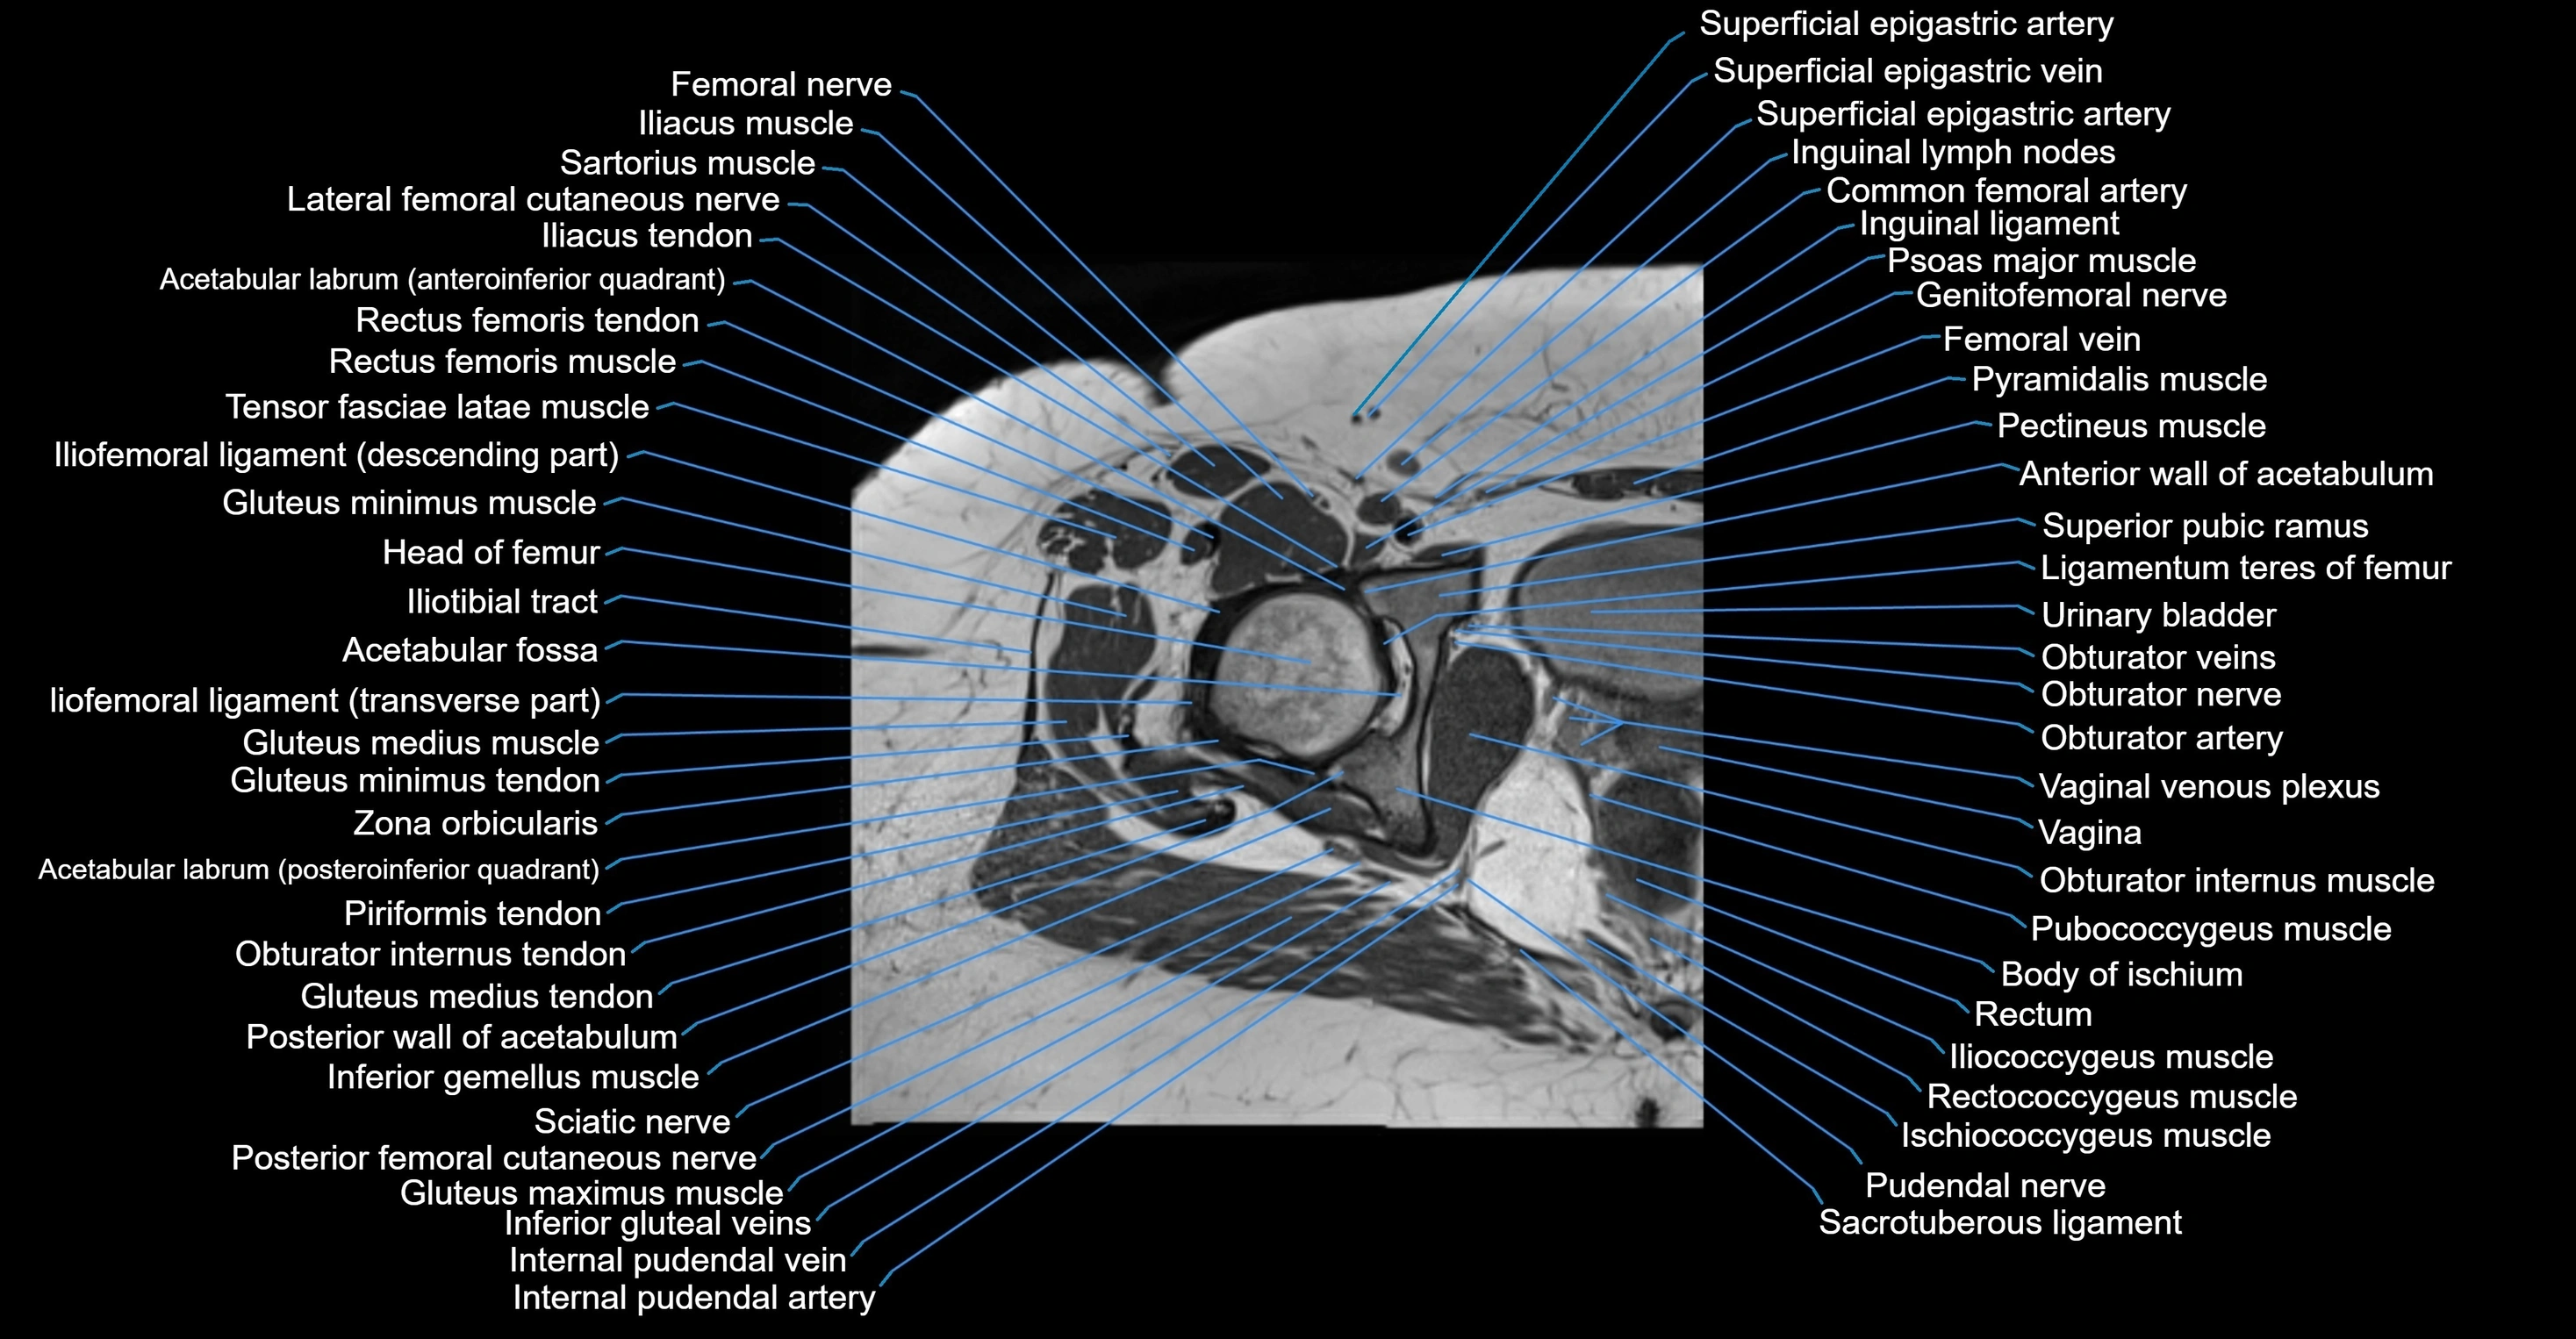

- Acetabular labrum

- Acetabulum

- Anterior wall of acetabulum

- Body of ischium

- Femoral nerve

- Femoral vein

- Gluteus maximus muscle

- Gluteus medius muscle

- Gluteus minimus muscle

- Gluteus minimus tendon

- Greater trochanter

- Head of femur

- Iliococcygeus muscle

- Iliofemoral ligament

- Iliopsoas muscle

- Iliopsoas tendon

- Iliotibial tract

- Inferior gemellus muscle

- Inferior gluteal vein

- Inguinal ligament

- Inguinal lymph nodes

- Ischiococcygeus muscle

- Ligamentum teres (ligament of the head of femur)

- Obturator externus muscle

- Obturator internus muscle

- Obturator internus tendon

- Obturator nerve

- Obturator vein

- Obturator veins

- Pectineus muscle

- Posterior femoral cutaneous nerve

- Psoas major muscle

- Pubococcygeus muscle

- Pudendal nerve

- Pyramidal muscle (pyramidalis muscle)

- Rectum

- Sacrotuberous ligament

- Tensor fasciae latae muscle

- Urinary bladder

- Vagina

- Vaginal venous plexus

- Zona orbicularis ligament